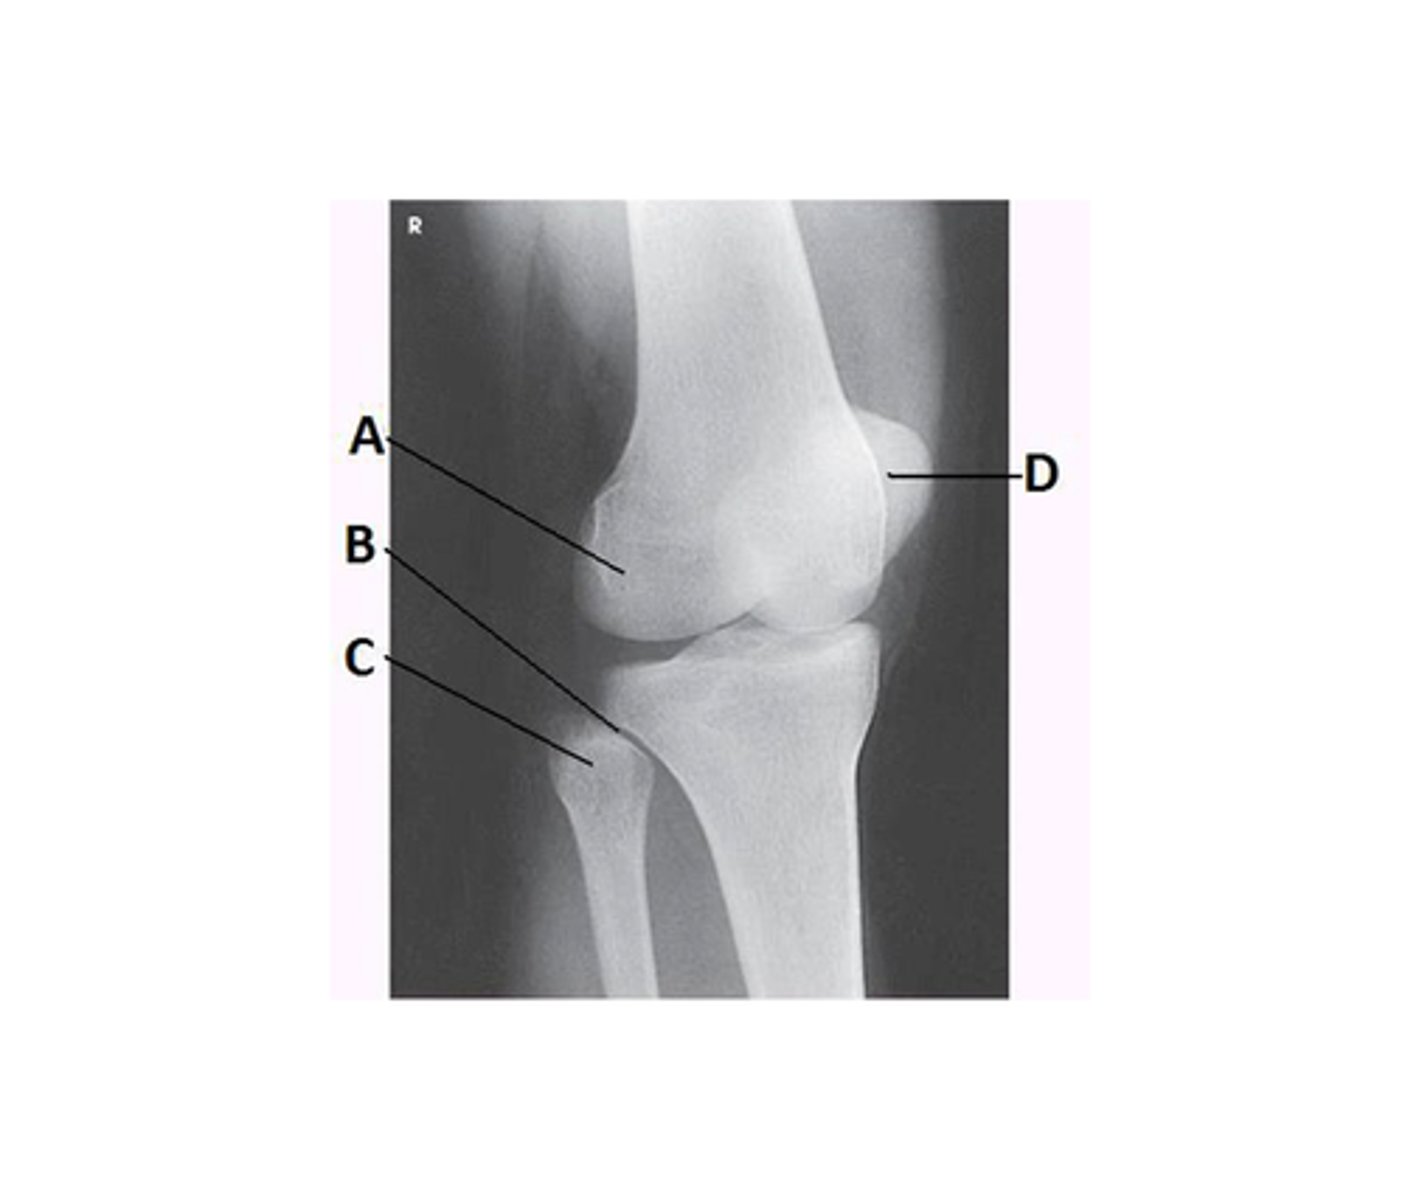

What anatomy is labeled with the letter B in the image below?

Proximal tibiofibular joint

What lower limb position is required to obtain the image below?

45-degree medial rotation

What anatomy is best demonstrated on an AP oblique knee, medial rotation?

Prox tib/fib joint, head of the fibula, and lateral condyles